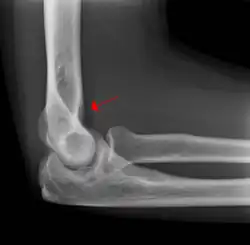

The fat pad sign, also known as the sail sign, is a potential finding on elbow radiography which suggests a fracture of one or more bones at the elbow. It may indicate an occult fracture that is not directly visible. Its name derives from the fact that it has the shape of a spinnaker (sail).[1] It is caused by displacement of the fat pad around the elbow joint. Both anterior and posterior fat pad signs exist, and both can be found on the same X-ray.

In children, a posterior fat pad sign suggests a condylar fracture of the humerus. In adults it suggests a radial head fracture.

The fat pad sign is invaluable in assessing for the presence of an intra-articular fracture of the elbow. An anterior fat pad is often normal. However a posterior fat pad seen on a lateral x-ray of the elbow is always abnormal. The patient will be unable to flex their elbow and requires orthopaedic input.[2]

The posterior fat pad is normally pressed in the olecranon fossa by the triceps tendon, and hence invisible on lateral radiograph of the elbow.[3] When there is a fracture of the distal humerus, or other pathology involving the elbow joint, inflammation develops around the synovial membrane forcing the fat pad out of its normal physiologic resting place. This is visible as the "posterior fat pad sign" and is often the only visible marker of a fracture, particularly in the pediatrics population.